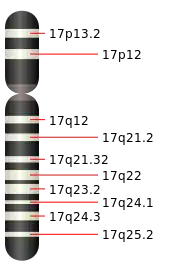

Chromosome 17 humain

Le chromosome 17 est un des 24 chromosomes humains. C'est l'un des 22 autosomes.